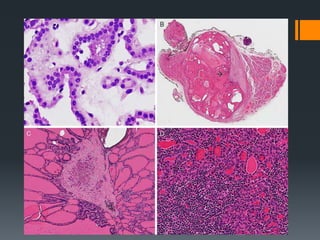

Psammoma Bodies

Hallmark of PTC

Basophilic concentrically laminated spherical

bodies.

The presence of psammoma bodies should prompt

a thorough search for other features of PTC

Identification of a psammoma body in a

perithyroidal or cervical lymph node is a sign of

micrometastatic PTC – Deeper levels.

Follicular epithelial neoplasm that exhibits capsular

and/or vascular invasion in the absence of nuclear

features of PTC is diagnosed as FTC.

Many pathologists consider a single focus of capsular

invasion to be a sign of malignancy when nuclear

features of PTC are absent.

Others have questioned if capsular without vascular

invasion qualifies for a diagnosis of a malignancy??

Most experts require the presence of tumor penetrating

through the entire thickness of the capsule of a lesion,

others consider it sufficient to identify the presence of

incomplete capsular Transgression.

Sites of previous biopsy can result in artefactual

capsular dehiscence and pseudoinvasion.

Bulging of tumor under intact endothelium,

intravascular tumor casts without thrombus and

intravascular tumor nests covered with intact

endothelium do not predict metastatic behavior.

Tumor cells invading through a vessel wall and

thrombus adherent to intravascular tumor predicts

an unusually high risk of distant hematogenous

spread.